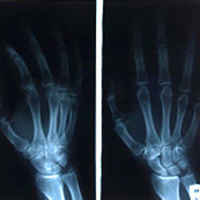

The Devestating Effects Of Carpal Tunnel Syndrome – CTS

Carpal Tunnel Syndrome (CTS) is a devastating disorder that is one of many listed under the general term, “Repetitive Strain Injury” (RSI). Of all repetitive strain injuries, carpal tunnel syndrome is the most recognized and prevalent among the general populace. And due to this recognition, many people are concerned about being afflicted with carpal tunnel…

What Causes Carpal Tunnel

A common factor in developing carpal tunnel symptoms is increased hand use or activity. While repetitive activities are often blamed for the development of Carpal Tunnel, the correlation is often unclear. Physiology and family history may have a significant role in individual’s susceptibility. Many cases of carpal tunnel syndrome are provoked by repetitive grasping and…